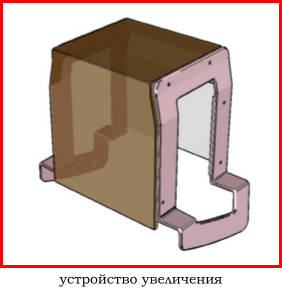

4.1 обычно отсутствует возможность съемки с увеличением (специальное устройства - столик),

4.1 наличие принадлежностей для съемки с увеличением,

В зависимости от высоты устройства достигается коэффициент геометрического увеличения объекта исследования 1.5х, 1.8х или 2.0х.

Метод прицельной маммографии с увеличением применяется для более детального исследования определенной области молочной железы. Он отличается высокой точностью диагностики. В отличие от обычной маммографии, которая предоставляет более общую информацию о состоянии молочных желез, прицельная маммография с увеличением позволяет получить точные данные о процессах, происходящих в тканях, благодаря методу компрессии конкретного участка.